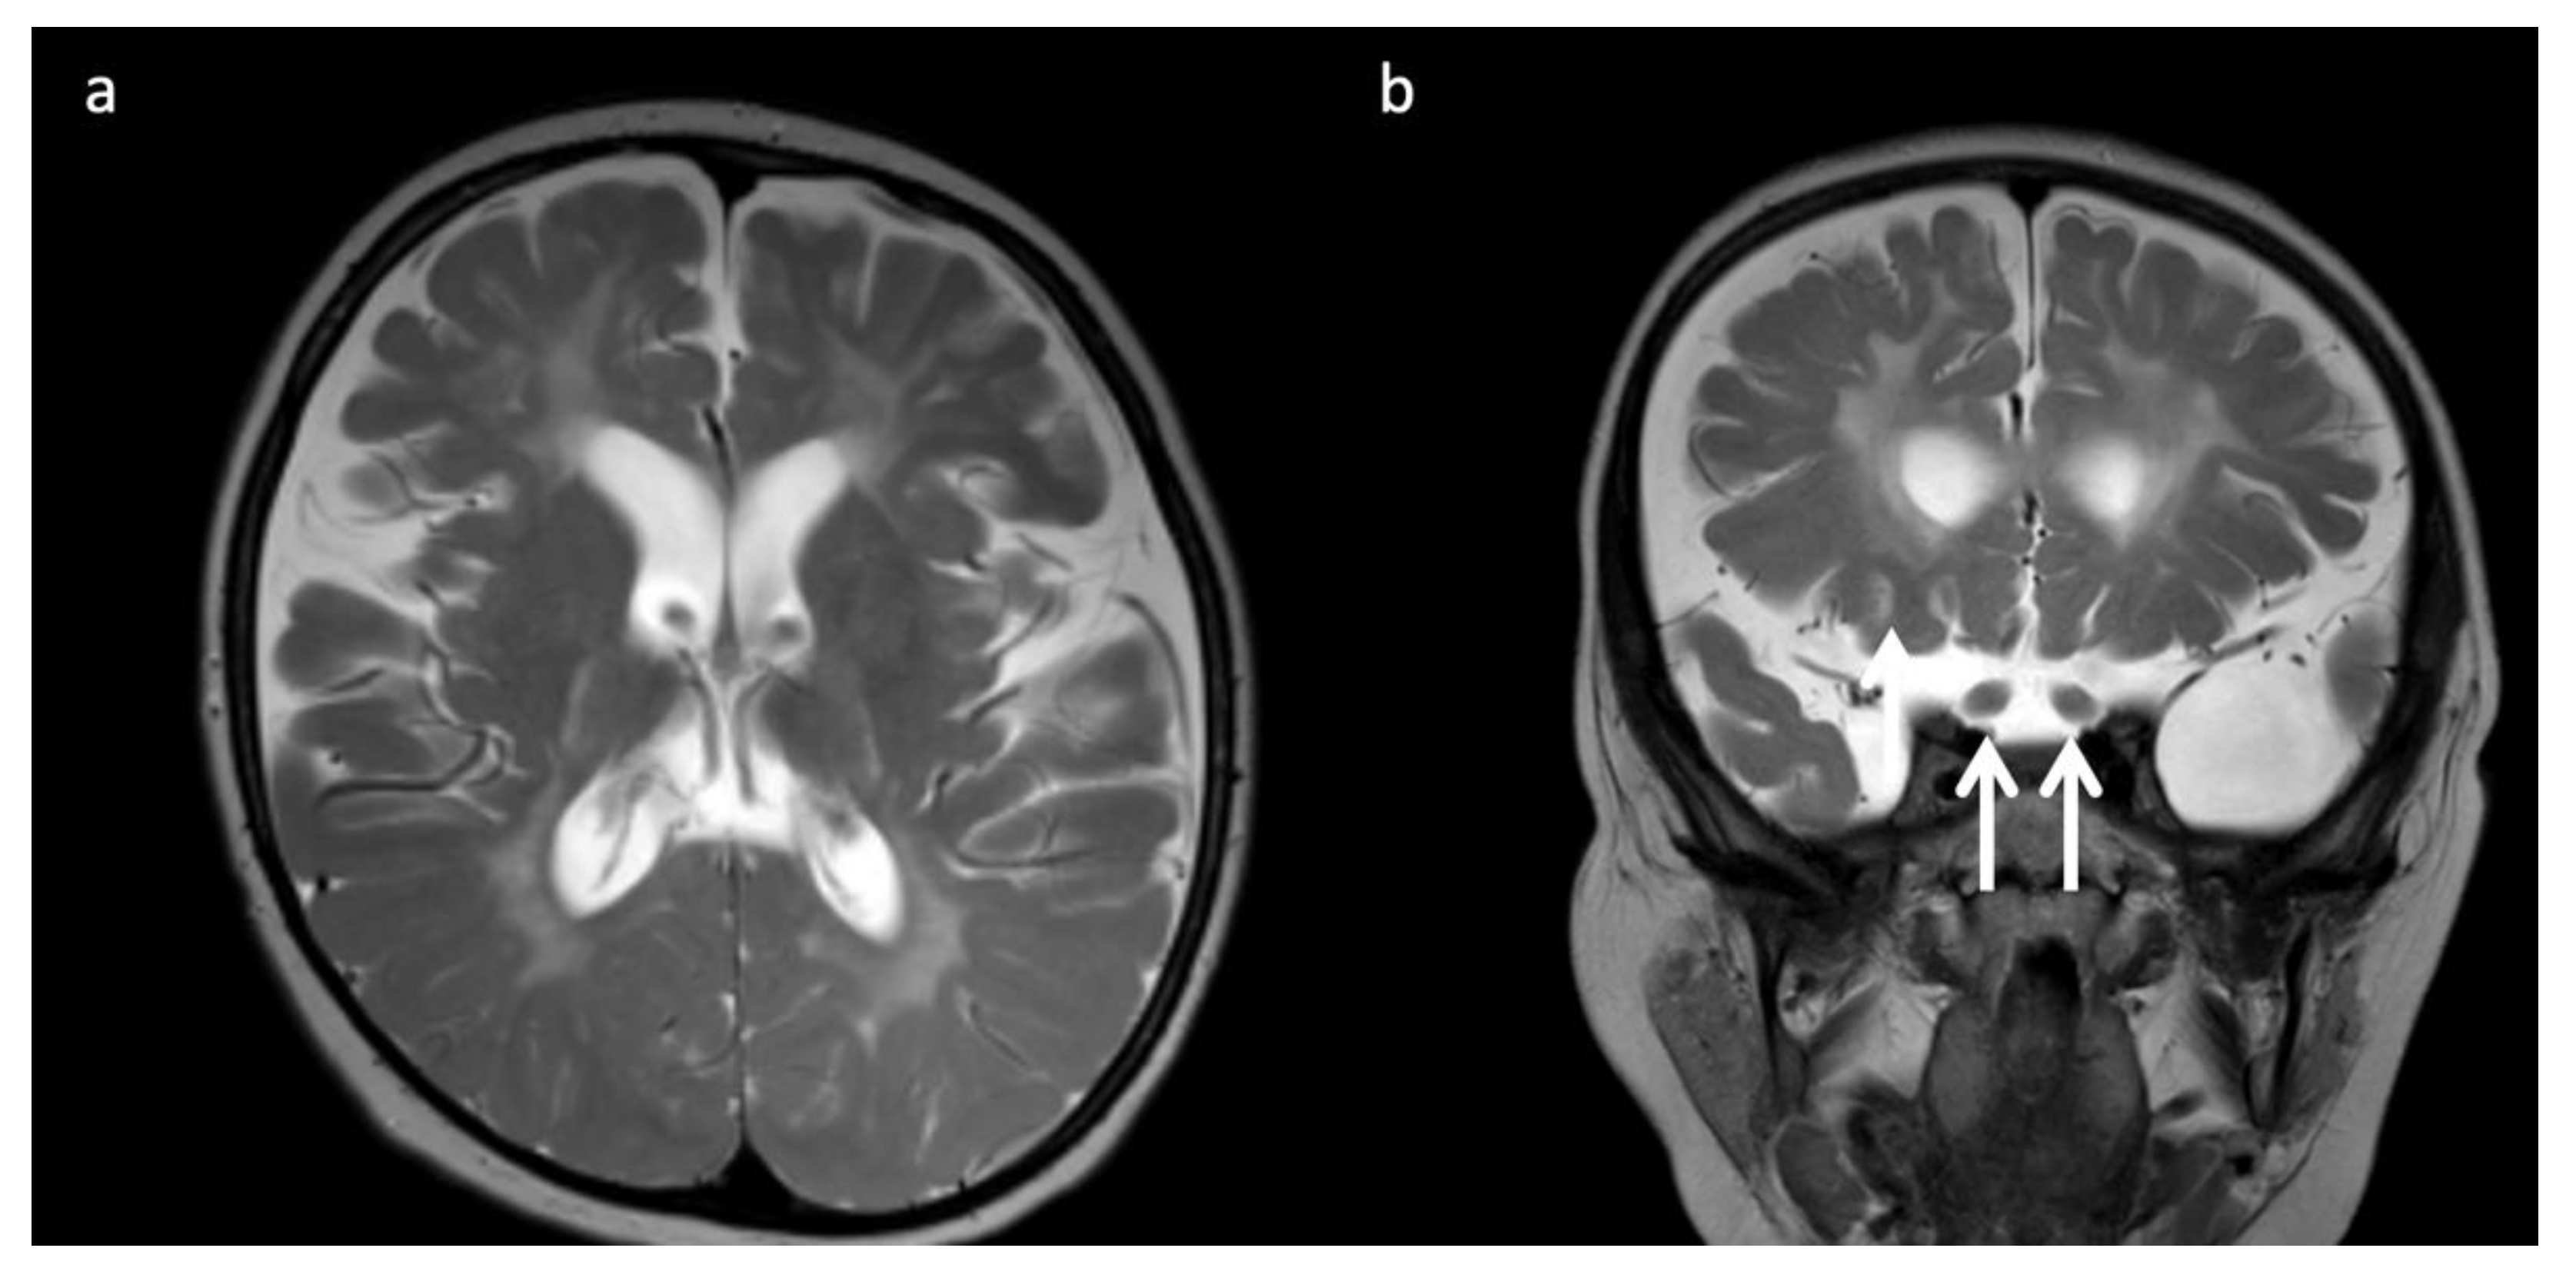

Lysosomal storage disease: GM2 gangliosidoses, including Tay-Sachs disease and Sandhoff disease (Figure 5), can show characteristic T2 hypointensity in the ventral thalami and T2 hyperintensity in the basal ganglia and dorsal thalami [28]. Krabbe disease (Figure 6) may show diffuse thalamic T2 hypointensity extending to the corticospinal tracts, as well as signal abnormalities in the cerebral and cerebellar white matter, especially the dentate hila and posterior cerebral white matter (centrifugal and posteroanterior gradient often with a tigroid pattern) and variable enlargement of the optic nerve and chiasm due to accumulation of globoid cells; MR phenotypes vary with age [3,8,10,29]. Post-contrast enhancement of multiple cranial nerves and the cauda equina is also characteristic. Metachromatic leukodystrophy (Figure 7) and Krabbe disease may have overlapping imaging features; however Krabbe disease typically spares the callosal genu and more often involves the internal capsules and brainstem [30]. Neuronal ceroid lipofuscinosis may also demonstrate thalamic T2 hypointensity, with cortical atrophy as another prominent feature [9].

Figure 6.

Three-year-old child with Krabbe disease and frequent seizures. Deficiency of lysosomal galactocerebroside β-galactosidase (GALC) results in accumulation of toxic psychosine. “Globoid” cells, macrophages containing galactocerebrosides, can be found in enlarged optic nerves. (a) Axial and (b) coronal T2WI show cerebral volume loss with ex vacuo ventriculomegaly, a widespread leukodystrophy with increased white matter signal sparing the U-fibers and corpus callosum, and thickening of the optic chiasm (arrows, b).